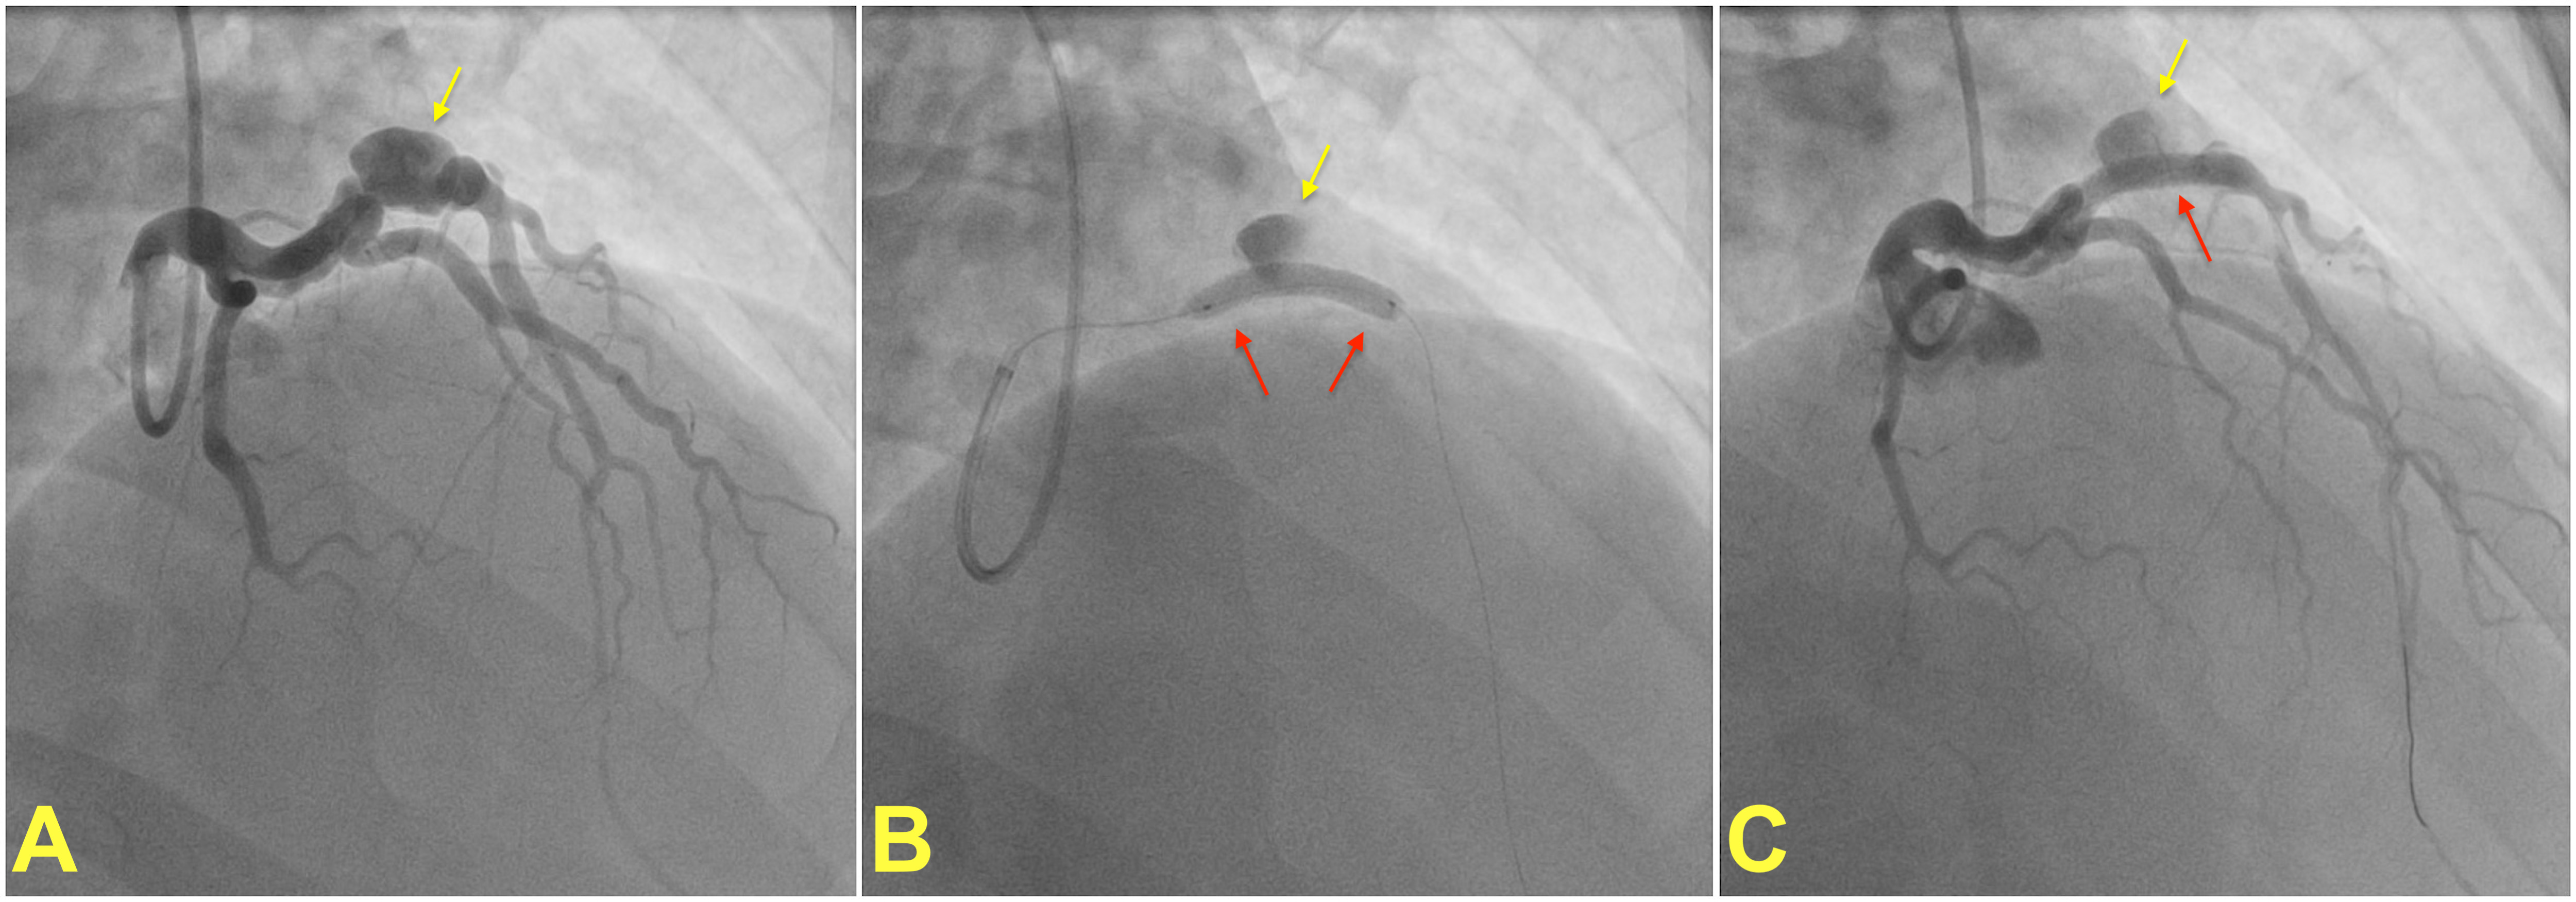

The aim of combining a stent with coil embolization is to maintain the patency of the flow within the main branch while simultaneously sealing off the aneurysm. It is mostly preferred when the CAA involves a major side branch artery, for bifurcation lesions and wide-neck aneurysms [43, 44, 45]. Stent graft is an alternative technique and is often preferred to seal relatively small saccular aneurysms when the coronary anatomy is suitable [46, 47] (Fig. 2). However, due to their stiff nature, stent grafts are not ideal for tortuous or severely calcified diseased vessels, as they may pose a risk of coronary dissection. Other concerns associated with covered stents include the closure of nearby side branches close to the aneurysm site, stent thrombosis, and the recurrence of restenosis [4, 48].

Fig. 2.

Percutaneous treatment of a coronary artery aneurysm. (A) shows coronary angiogram of a patient with a saccular coronary aneurysm (yellow arrow) on the left anterior descending artery. A covered stent (red arrow) is placed and deployed to isolate the aneurysm from the coronary circulation (B). (C) shows the final result after post-dilatation of the covered stent with a noncompliant balloon. Note that the contrast within the aneurysm is residual and does not indicate stent failure. Images courtesy of Dr. Muslum Sahin.